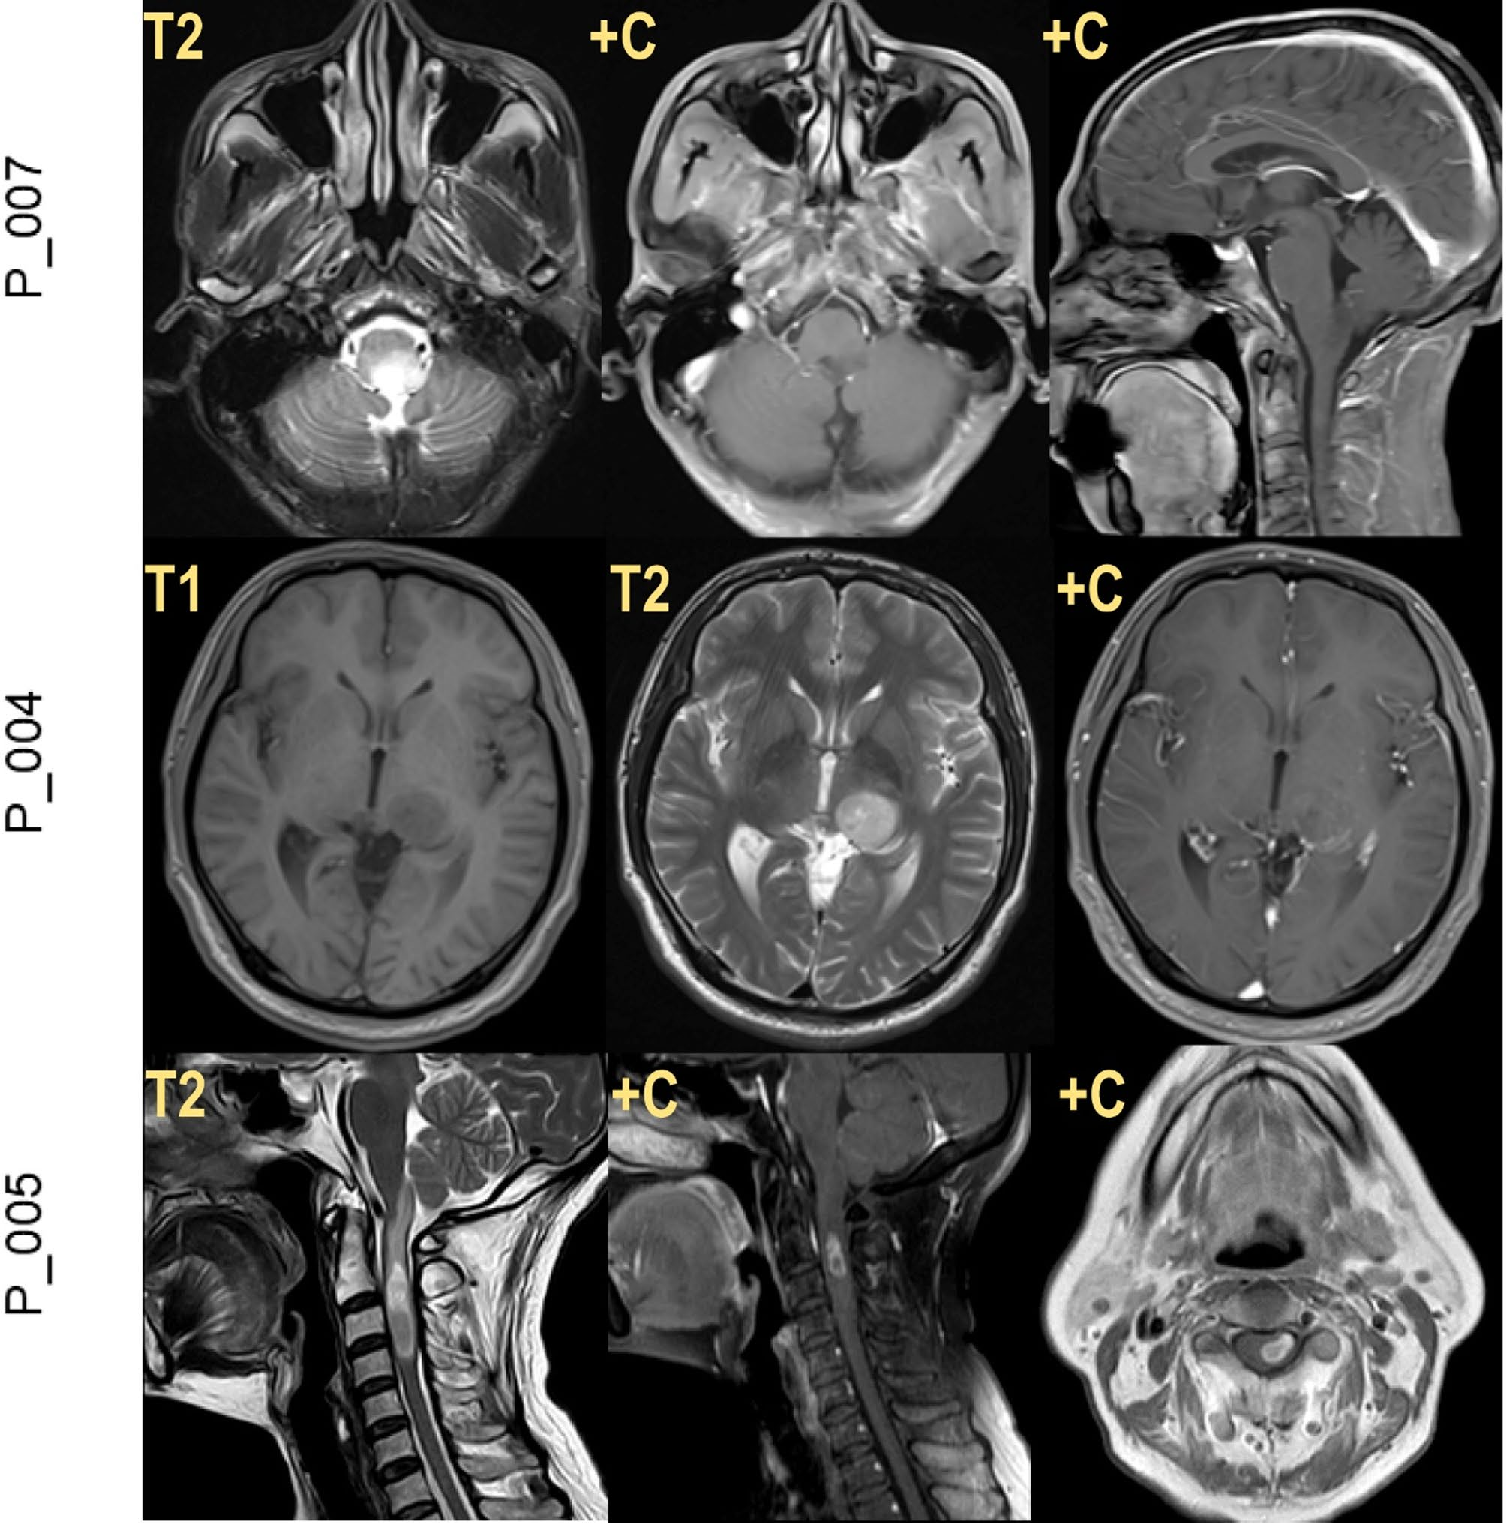

研究纳入的所有13例H3F3B突变型DMG患者,包括9名男性和4名女性,平均诊断年龄为46岁±6.86岁,显著高于H3K27M突变型DMG患者。 从解剖学分布看,这13例分别为6例脊髓、5例脑干、2例丘脑受累(图1)。

本地队列9例患者,病理组织学评估发现肿瘤样本形态学具有异质性,3例为弥漫性星形细胞瘤、3例为间变性特征、其余3例均为胶质母细胞瘤特征。IHC结果显示,所有样本均显示H3K27M免疫染色阴性、完全/镶嵌样H3K27me3表达缺失、且无EZHIP (CXorf67)表达或ATRX表达缺失现象(图1)。

图1. H3F3B p.K27I突变型DMG的影像及病理学特征